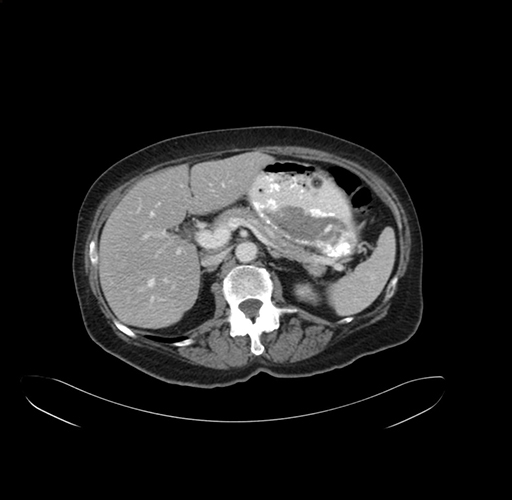

Pre-Chemo: Axial Venous

Axial Venous